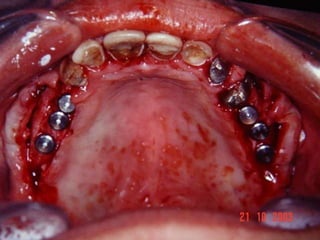

Implantes Em Áreas Com Pouco Volume Ósseo

Mandíbula Parcialmente EdentadaQualidade do ossoPosição do feixe neurovascularComprimento dos implantesTamanho do espaço edentadoTipo de carga oclusal

Avaliação da Altura e Largura óssea